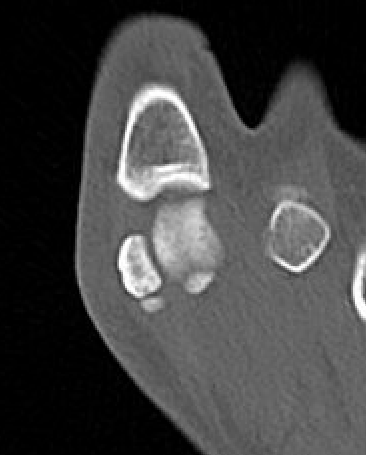

CT demonstrates irregular borders consistent with fracture of tibial sesamoid